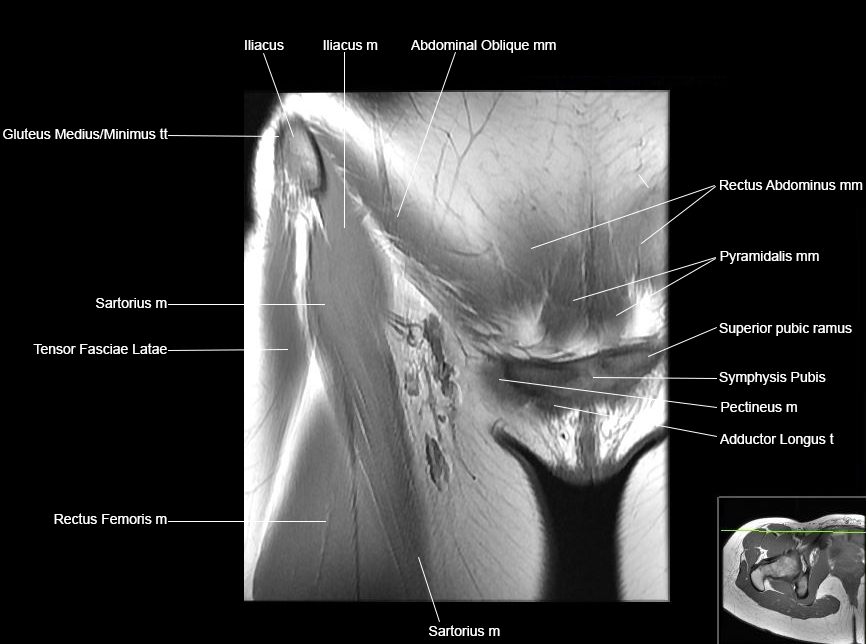

Hip

Basic Hip MRI

MRI Hip Anatomy

Scroll using the mouse wheel or the arrows